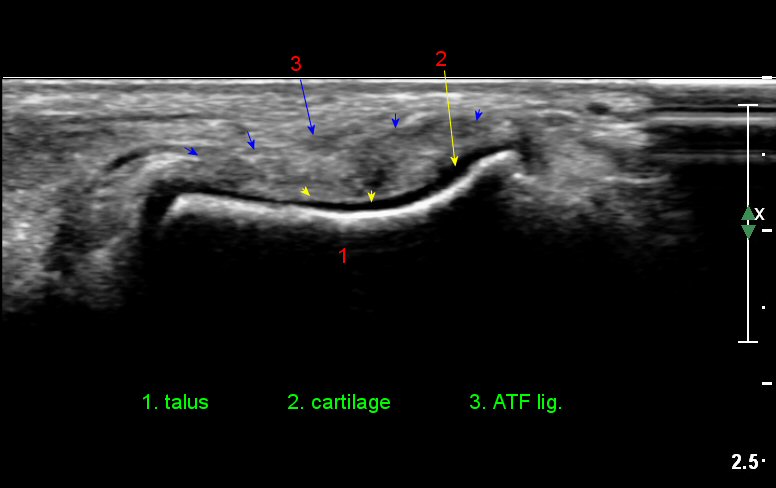

¹ß¸ñ°üÀý ¾ÕÂÊ Á¾´Ü¸é°Ë»ç¿¡¼­ ƯÀÌ ¼Ò°ßÀ» º¸ÀÌÁö ¾ÊÀ¸³ª(»çÁø 1)

ŽÃËÀÚ¸¦ ÀÎÁ¢ÇÑ ºÎÀ§·Î À̵¿ÇÏ´Ï ¼Ò·®ÀÇ °üÀý³» ¼ö¾×Àú·ù°¡ °üÂûµÈ´Ù(»çÁö 2).

Àü¹æ °æ°ñºñ°ñÀδë Á¾´Ü¸é°Ë»ç¿¡¼­ ƯÀÌ ¼Ò°ßÀ» º¸ÀÌÁö ¾Ê´Â´Ù(»çÁø 3).

Àü°ÅºñÀδë Á¾´Ü¸é°Ë»ç¿¡¼­ ¾È´ë ºñ°ñ ºÎÂøºÎÀÇ Àú¿¡ÄÚ ºÎÁ¾°ú ºÎºÐÆÄ¿­ÀÌ °üÂûµÈ´Ù(»çÁø 4).